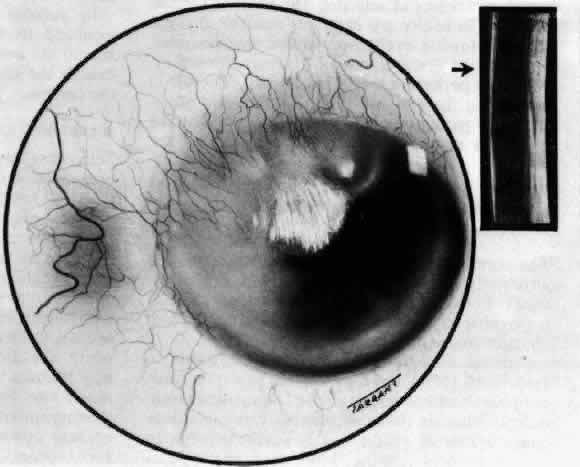

The sclera that is edematous is pushed forward, and the deep episcleral network is more congested than the superficial networks (Figs. 27 and 28). It is usually easy to ascertain by simple observation that the patient has scleritis and not episcleritis. However, it is not as easy to ascertain whether the patient has early necrotizing scleritis. It is in these patients that fluorescein angiography has considerable value, because the first changes are detectable in the ocular vasculature. Prompt and adequate treatment can prevent these changes from becoming irreversible.

Fig. 27. In scleritis, maximum congestion occurs in deep episcleral plexus, which is bowed forward by underlying scleral edema. Episcleral tissue is slightly infiltrated and superficial plexus is slightly congested (see Fig. 14). (Watson PG, Hayreh S, Awdry P: Episcleritis and scleritis. Br J Ophthalmol 52:278–279, 1968)

Fig. 28. Nodular scleritis. Both the anterior conjunctival slit and the deep scleral slit are displaced forward by the scleral edema. There is little separation between these two beams, indicating that all the edema is in the sclera and not in the overlying episclera. (Watson PG, Hayreh S, Awdry P: Episcleritis and scleritis. Br J Ophthalmol 52:278–279, 1968)